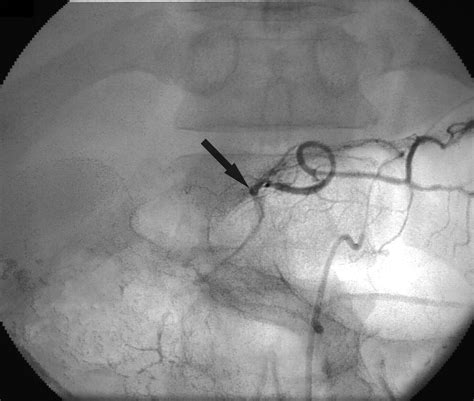

• Digital Subtraction Angiography (DSA): DSA is an invasive procedure that involves injecting a contrast agent into the blood vessels and using X-ray imaging to visualize the vascular anatomy. It is often used in interventional radiology procedures to guide embolization or other treatments.

One of the most common interventional radiology procedures involving the LGA is embolization. Embolization involves blocking the blood supply to a tumor or bleeding site to reduce its size or stop the bleeding. This procedure can be performed using various embolic agents, such as coils, particles, or liquid embolic agents.

Embolization of the LGA is often used in the treatment of gastric cancer to reduce the tumor's blood supply and facilitate surgical resection or other treatments. It can also be used to manage gastrointestinal bleeding, particularly in cases where the bleeding site is difficult to access surgically.

Another interventional radiology procedure involving the LGA is stent placement. Stents are small, mesh-like tubes that can be placed in blood vessels to keep them open and maintain blood flow. Stent placement in the LGA can be used to treat stenosis or occlusion of the artery, which can occur due to various conditions such as atherosclerosis or tumor compression.